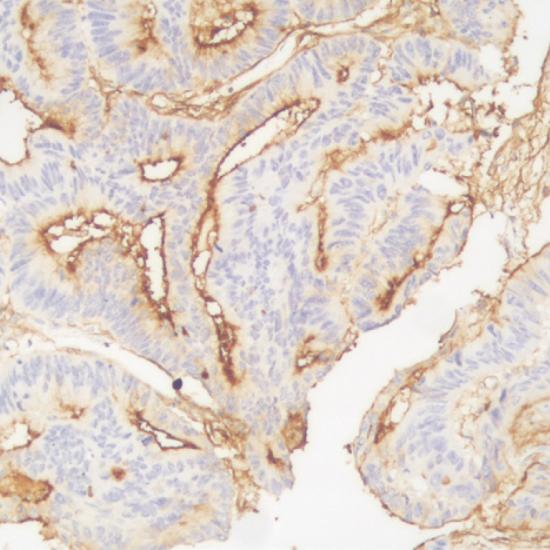

P170/Pgp/MDR-1

細(xì)胞膜

結(jié)腸癌

P170是MDR基因所編碼的一種膜型糖蛋白,屬ABC(ATP bindingcassette)超家族膜轉(zhuǎn)運(yùn)蛋白之一,可以由ATP供能將細(xì)胞毒類藥物快速泵至細(xì)胞外,其表達(dá)水平與細(xì)胞膜的通透型、細(xì)胞內(nèi)藥物濃度及細(xì)胞耐藥程度有關(guān)。腫瘤細(xì)胞P170的高表達(dá)提示腫瘤對部分親脂性藥物產(chǎn)生耐藥,對臨床化療具有指導(dǎo)意義。